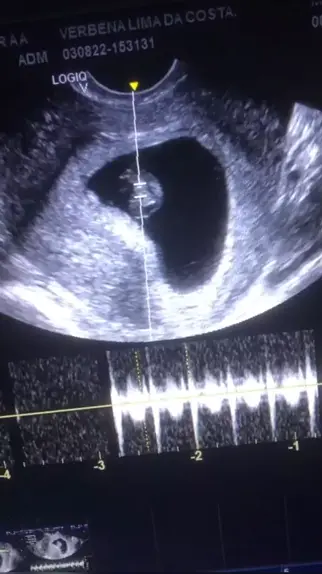

Verbena Lima

#primeiraultrassom π 6 semanas e 2 dias